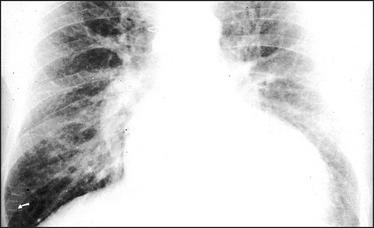

Figure 8.4 Interstitial pulmonary oedema The heart is moderately enlarged. The interstitial oedema causes fine, diffuse shadowing in the lung fields with blurring of the vessel margins. The escape of fluid into the interstitial tissue occurs when the capillary pressure exceeds the plasma osmotic pressure of 25 mmHg. The interstitial oedema is characterised by Kerley ‘B’ lines, which are oedematous interlobular septa. They are best seen peripherally in the right costophrenic angle (arrow), where they lie horizontally, and are about 1 cm long. They contain the engorged lymphatics, which were originally thought by Kerley to be the sole cause of the ‘B’ lines. Sternal sutures are present from previous cardiac surgery.